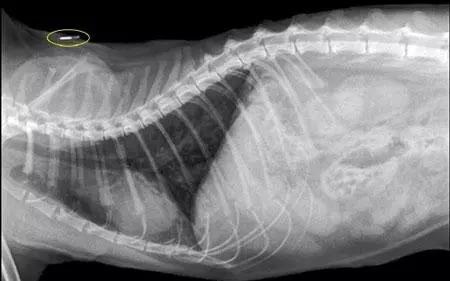

芯片本身不是什么黑科技,注射的时候也不需要麻醉和开刀。大小就跟米粒差不多,长度约为0.8~0.9cm,通过注射器植入到宠物皮下,用专用扫描仪在狗狗身上一扫就能知道是否植过芯片了。宠物芯片被植入到宠物体内,极少有丢失的情况,对宠物健康也是安全的, 是管理宠物、增加找回机会的合适选择。

最后,我们建议芯片由CKU授权的机构进行埋置,因为专业人员知道芯片应该打在什么地方,使用多少压力,因为如果方法不当可能会伤害到狗狗 。打芯片之前应先核对芯片号,植入之后也应读取芯片号,确保它植入的芯片号无误并且能够正常工作